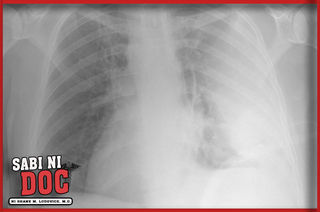

Ludovice MD Sabi ni Doc Dear Doc. May t u big sa b a g ng pat y na o so. Winz Sagot Ang tubig sa baga o kilala sa tawag na pulmonary edema ay kondisyon na napupuno ng tubig ang baga ng tao.

Sa malalang mga kalagayan ang mga taong may tubig sa baga ay kailangang gamutin sa intensive care unit o ICU. Saan ba ito nakukuha. Tubig sa baga.

Kerwin Store Taguig City. May mga ibang bagay na maaaring magdulot ng tubig sa baga - pneumonia exposure sa toxins injury sa chest wall o ang pag-ehersisyo sa matataas na altitude sakit sa puso at kidneys. Tagalog example sentence for Baga.

Dahilan ng PagsusukahttpsyoutubeI6Ukb6PAK-gLunas at dulot ng Diabeteshttpsyoutube3q6YPh6wEbgKidney Stoneshttpsyoutube21pij68MyaYRayuma at B. Maraming posibleng maging komplikasyon ang pagkakaron ng tubig sa baga kaya naman dapat na malaman ang mga sintomas para magamot agad at hindi na lumala. From professional translators enterprises web pages and freely available translation repositories.

Narito ang ilan sa mga pamamaraan ng panggagamot. Aspiration ito ay ang pag higop sa tubig sa baga gamit ang isang tubo na ipinapasok pababa sa lalamunan Diuretic o pampaihi ito ay gamot na ibinibigay upang mailabas ang tubig sa baga sa natural na paraan Gamot sa sakit sa. Human translations with examples.

Put your mouse over or tap for mobile devices any Filipino word to see its translation in English. Dahil sa naipon na tubig sa baga nahihirapan ang ating puso na mag-pump ng dugo at nahihirapan ang ugat na ipakalat ang oxygen at nutrients na kinakailangan ng ibang organ sa ating katawan. Chevron_right Log in.